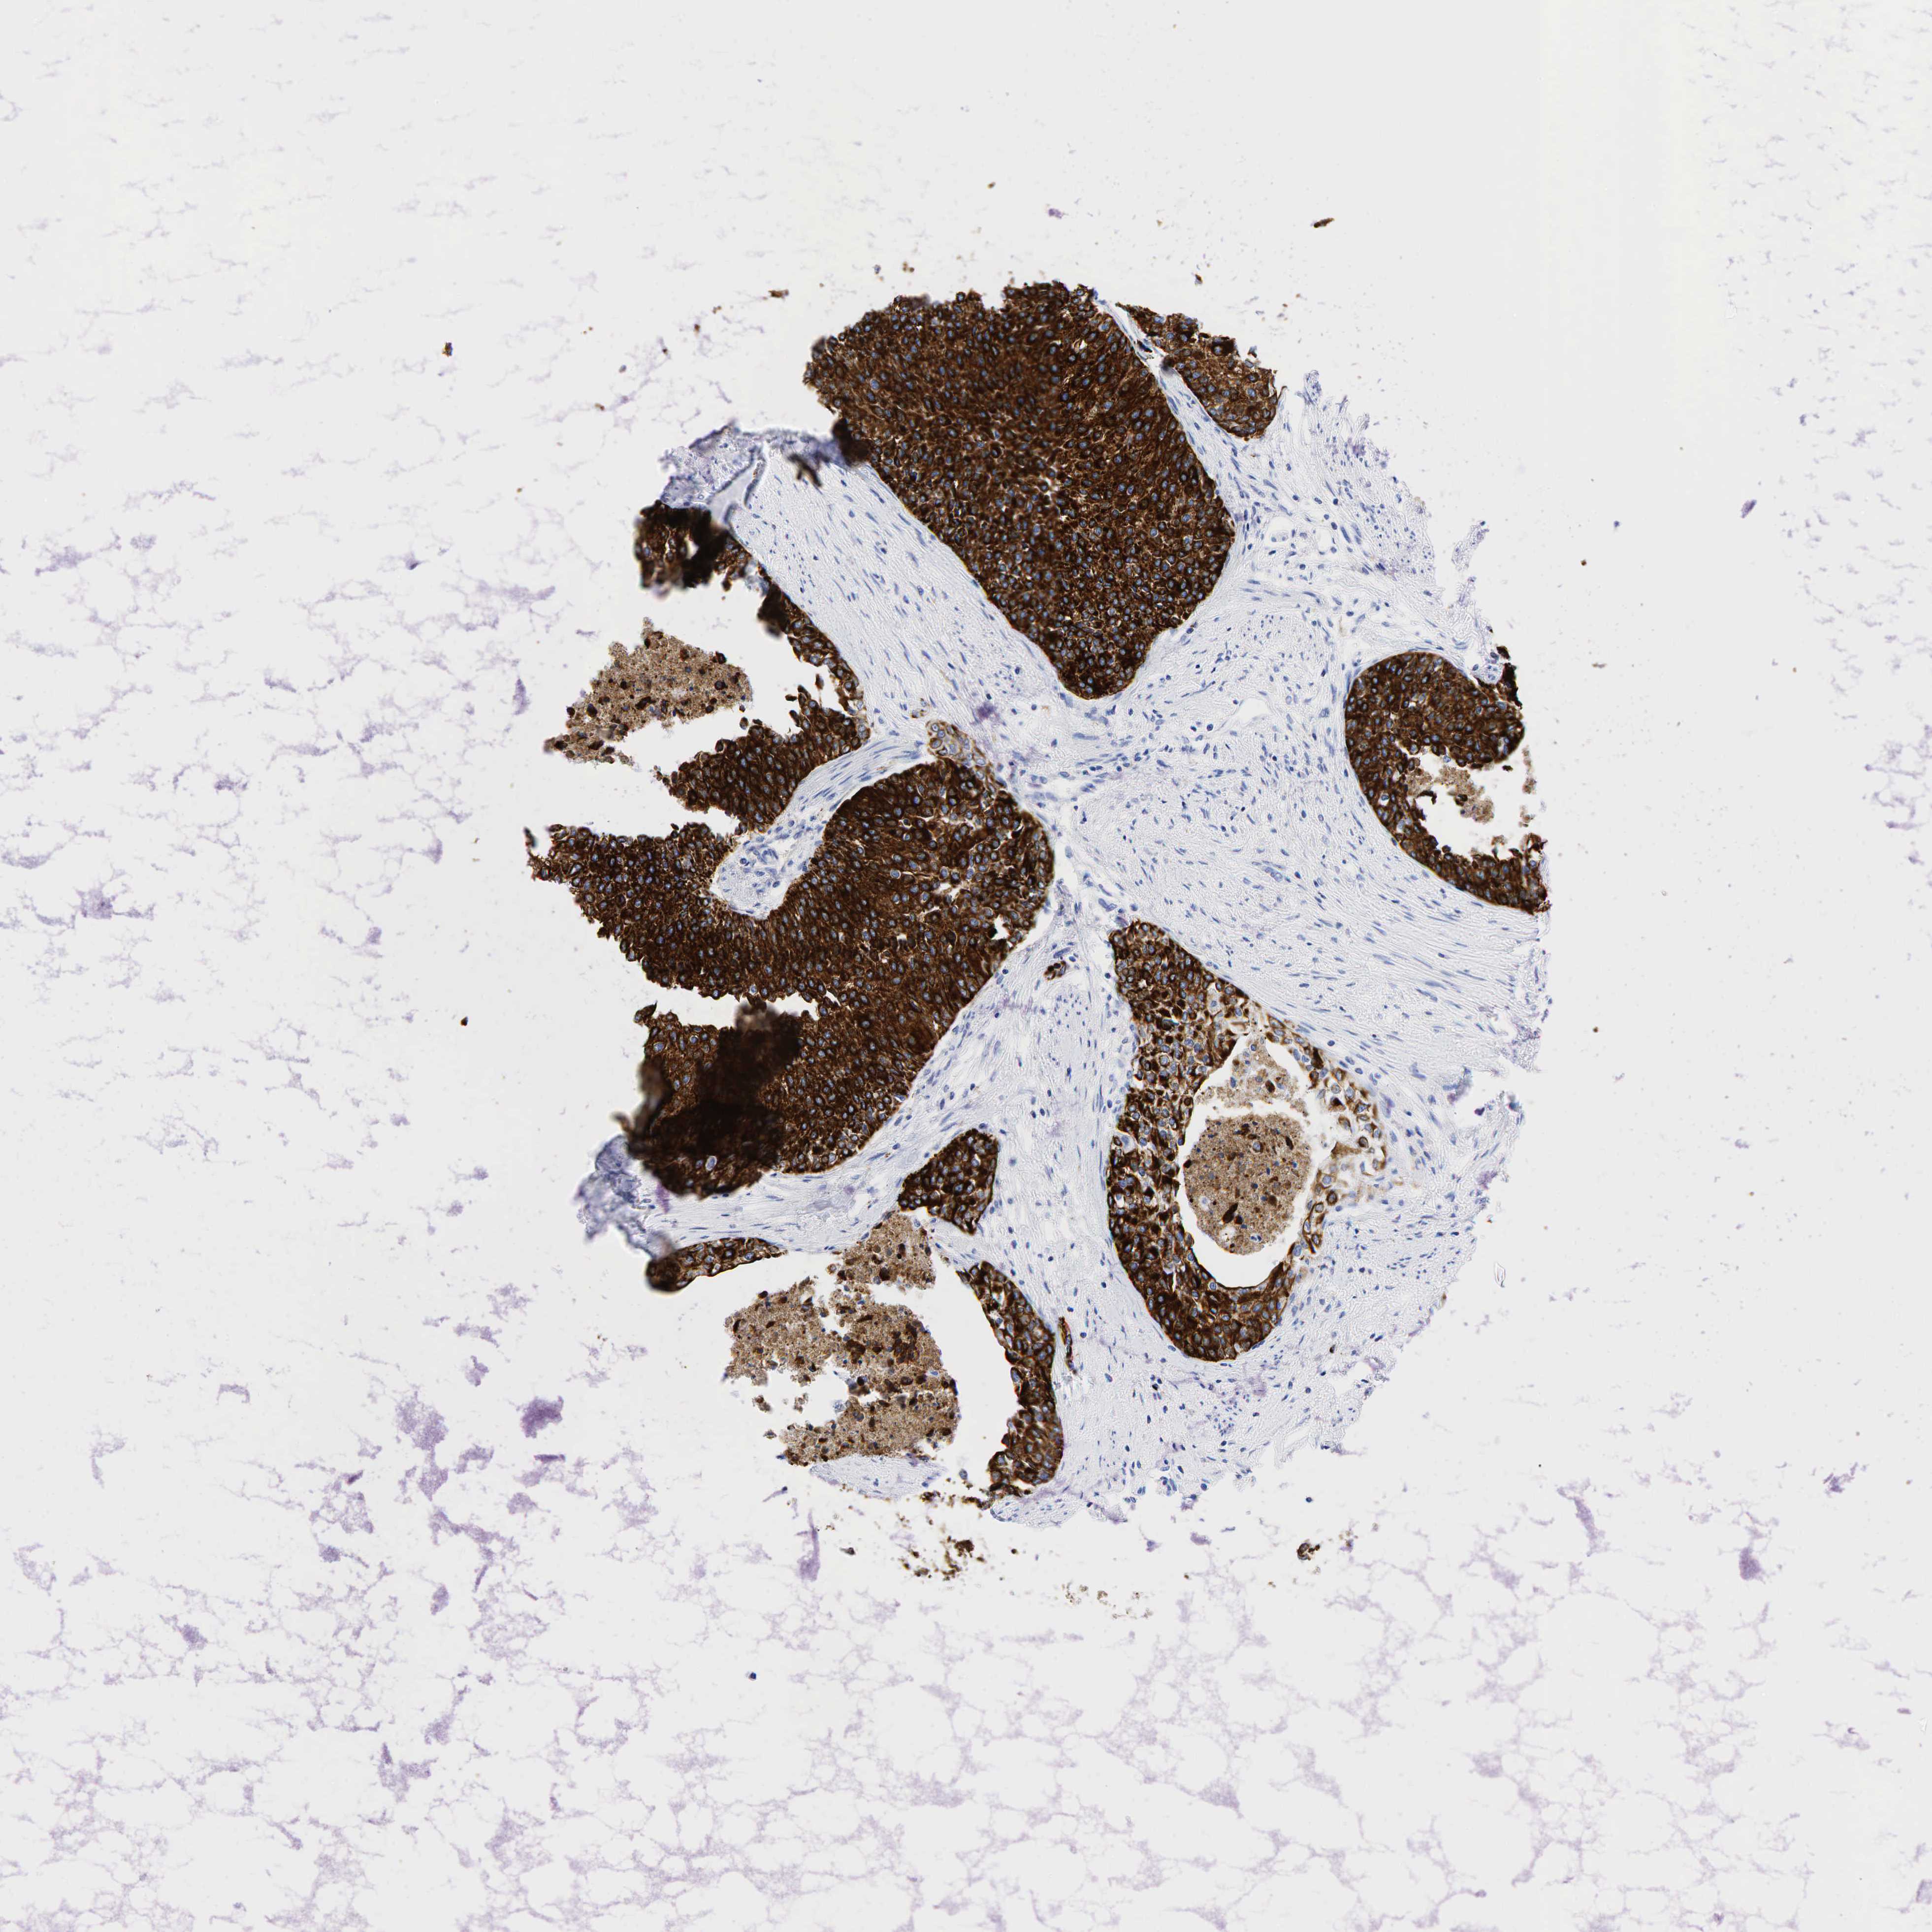

UROTHELIAL CANCER - Protein expressioni

A mouse-over function shows sample information and annotation data. Click on an image to view it in a full screen mode. Samples can be filtered based on level of antibody staining by selecting one or several of the following categories: high, medium, low and not detected. The assay and annotation is described here.

Note that samples used for immunohistochemistry by the Human Protein Atlas do not correspond to samples in the TCGA dataset.

Antibody stainingi

Antibody staining in the annotated cell types in the current human tissue is reported as not detected, low, medium, or high, based on conventional immunohistochemistry profiling in selected tissues. This score is based on the combination of the staining intensity and fraction of stained cells.

Each image is clickable and will lead to virtual microscopy that enables deeper exploration of all samples and also displays staining intensity scores, fraction scores and subcellular localization as well as patient and tissue information for each sample.

Antibody HPA002465

Antibody CAB000031

Urothelial carcinoma, High grade

Urothelial carcinoma, Low grade

Adenocarcinoma, NOS